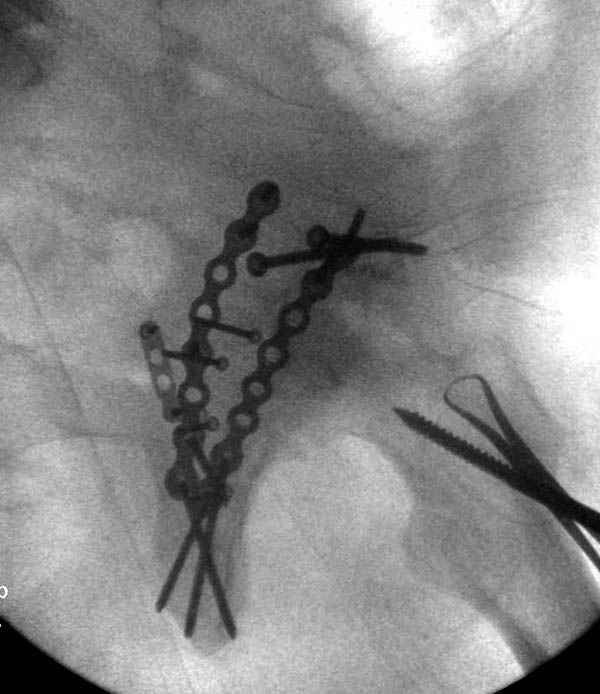

Дополнительно имеется перелом ацетабулума: задняя

колонна с полупоперечным переломом, и переломы костей лица.

На седьмой день зафиксирован перелом ацетабулума через задний доступ. Перед операцией для профилактики DVT, IVC фильтер, также получает Lovenox.

Там множество обычных 2.7 мм шурупов, потом идет фиксация основными пластинами.

Снимки здесь....